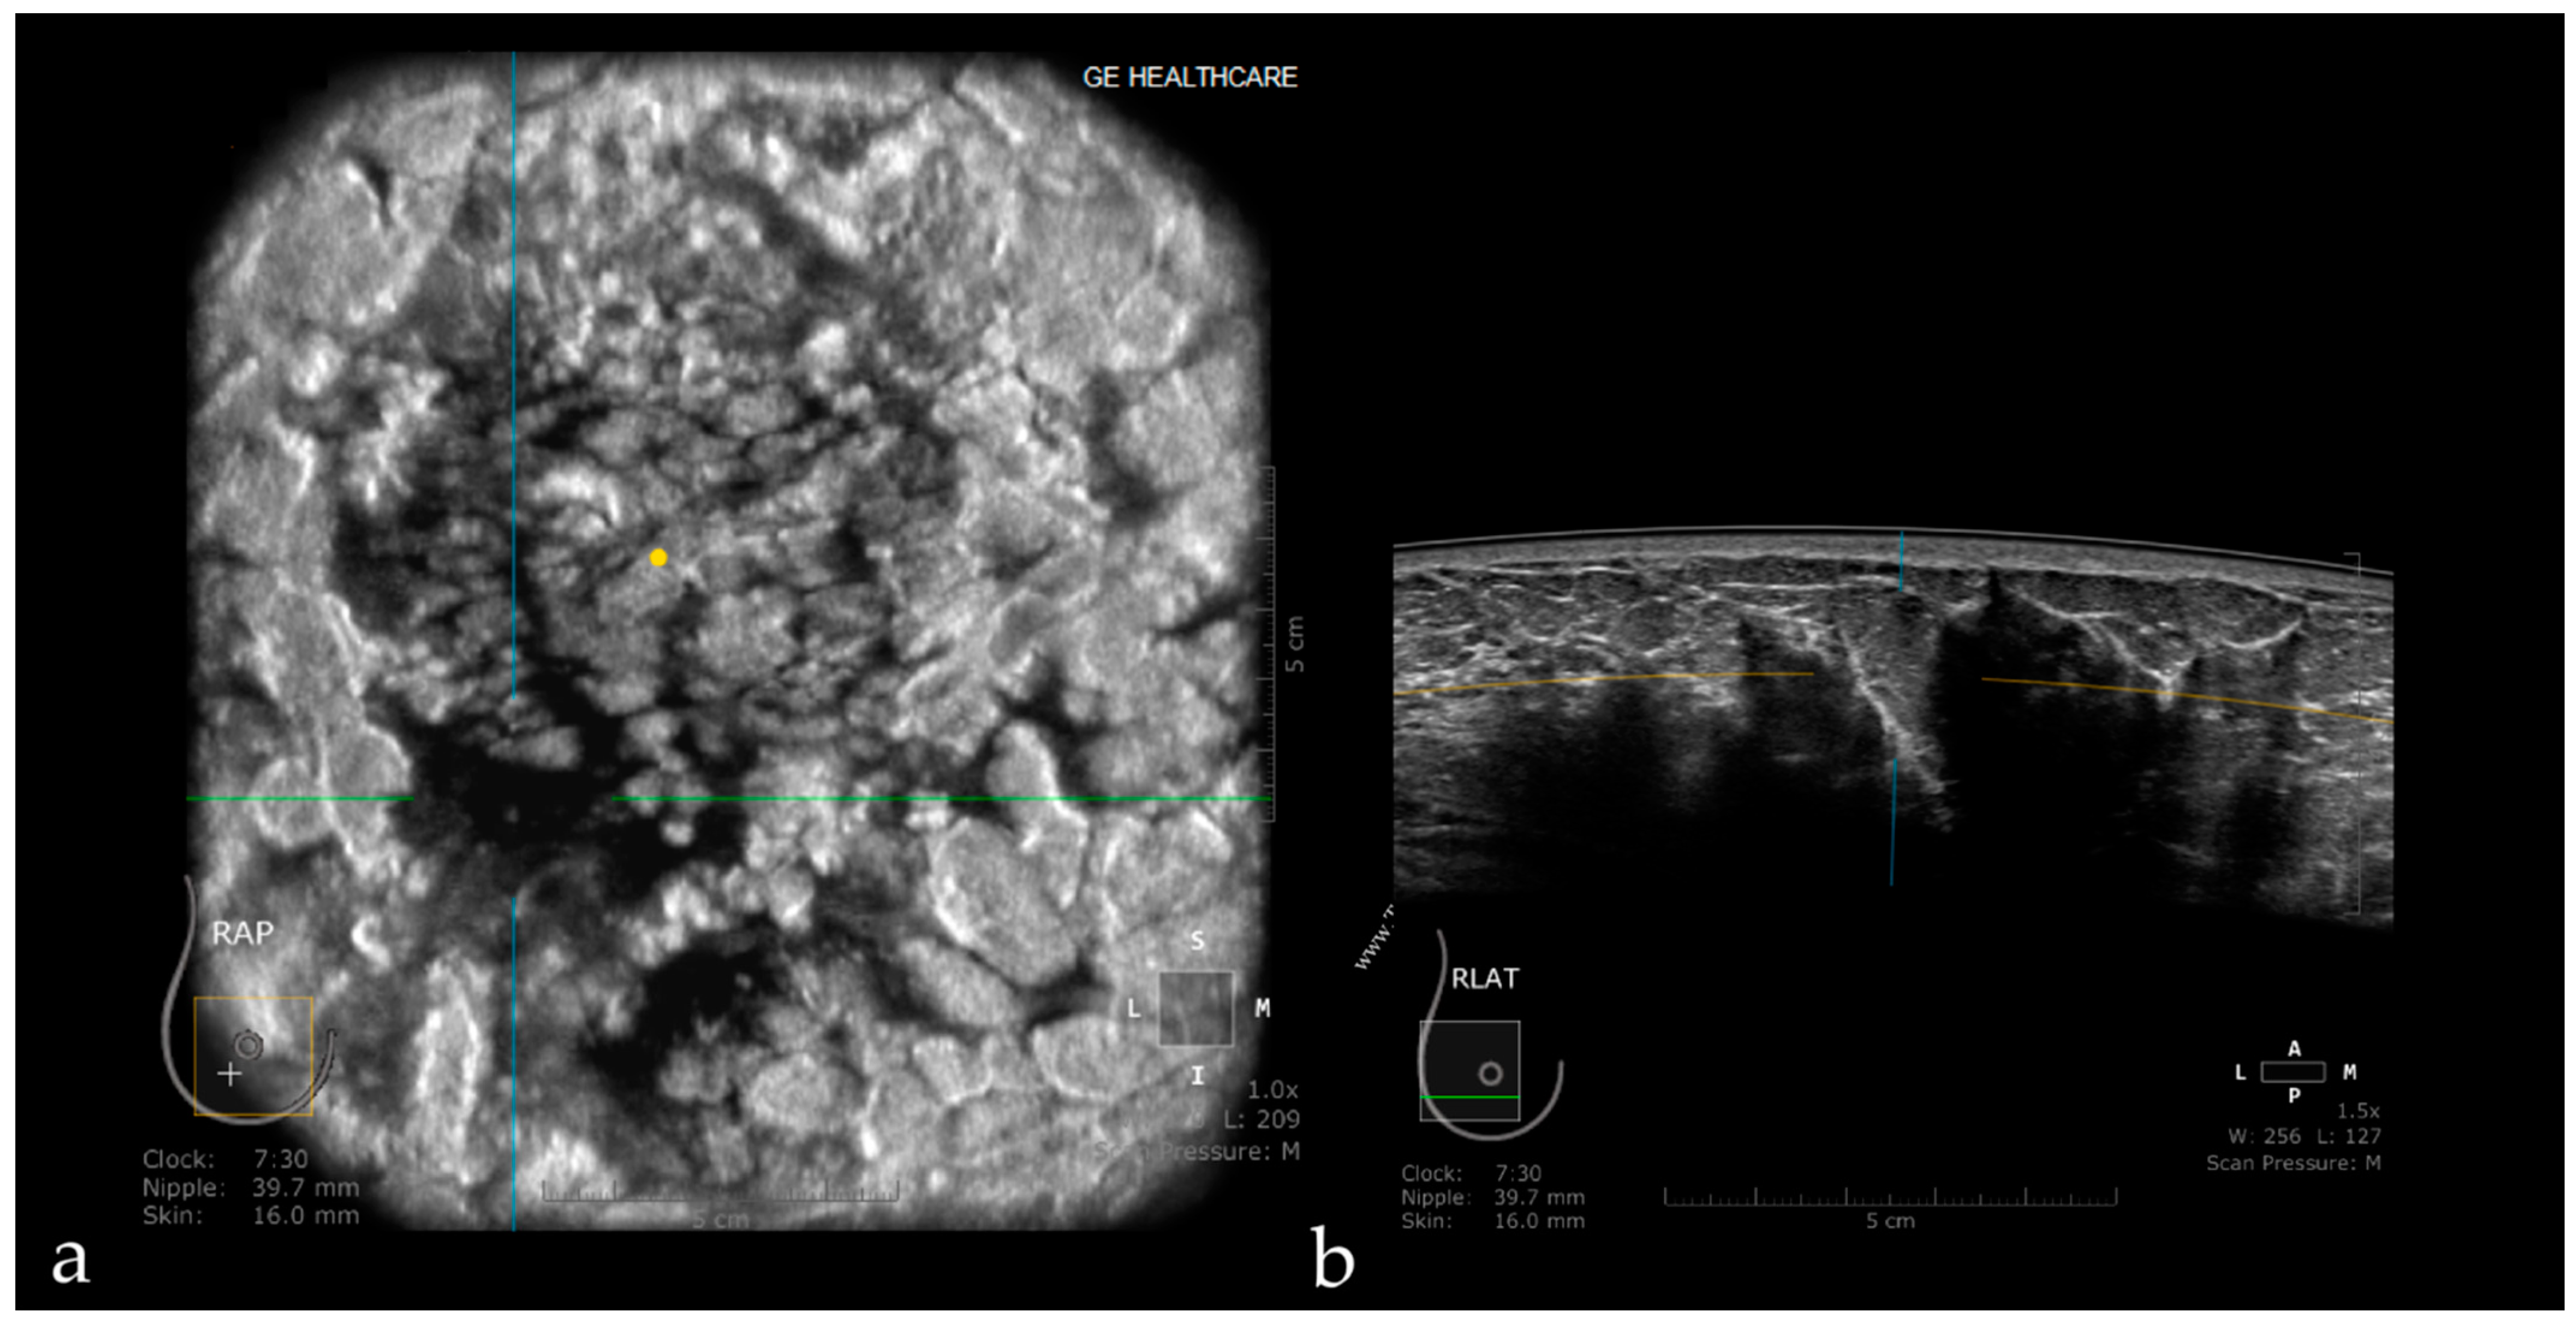

3.1. Technique and Artifacts

3.1.1. Limitations Related to the Technique

3.1.2. Artifacts

Artifacts Induced by the Use of Ultrasound Gel

Air Interposition

Insufficient Compression

Probe Motion Artifacts

Breathing Artifacts

Skip Artifact

Nipple Artifact

Attenuation Areas

White Wall Sign